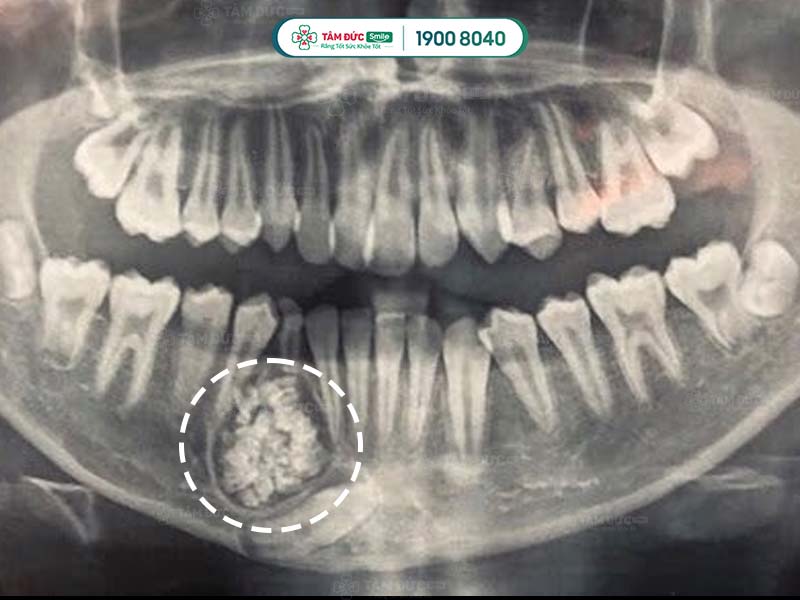

U răng qua phim chụp X-Quang

- U răng phức hợp giống như một khu vực cản quang với các mật độ u khác nhau ở từng dạng bệnh.

- Ở u răng đa hợp, răng vẫn còn 3 mô răng riêng biệt là: men răng, ngà răng và xương răng. Có thể vẫn có thùy răng.